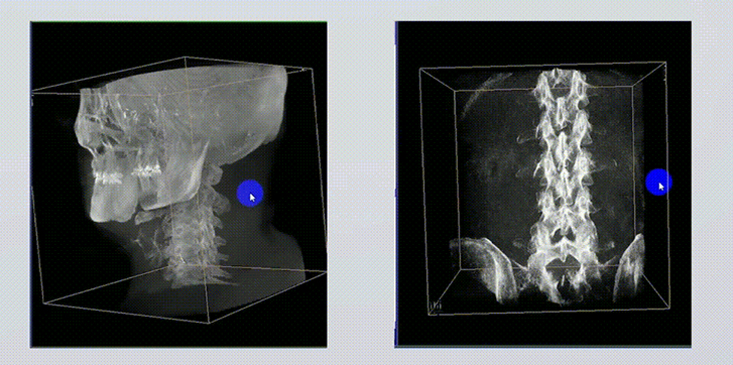

1、術(shù)中實時三維成像

術(shù)中三維成像和橫斷面圖像提供多角度的手術(shù)診斷信息,輔助醫(yī)生進行術(shù)中評估判斷,諸如骨折復位情況和內(nèi)植入螺釘?shù)某叽绾臀恢?,輔助手術(shù)更好地完成。

2、三維成像視野大

提供更大的術(shù)中三維成像視野,采集更多圖像信息,可一次拍全全段頸椎、全段腰椎、七節(jié)胸椎、雙側(cè)骶髂關節(jié)、股骨頭及單側(cè)盆骨。